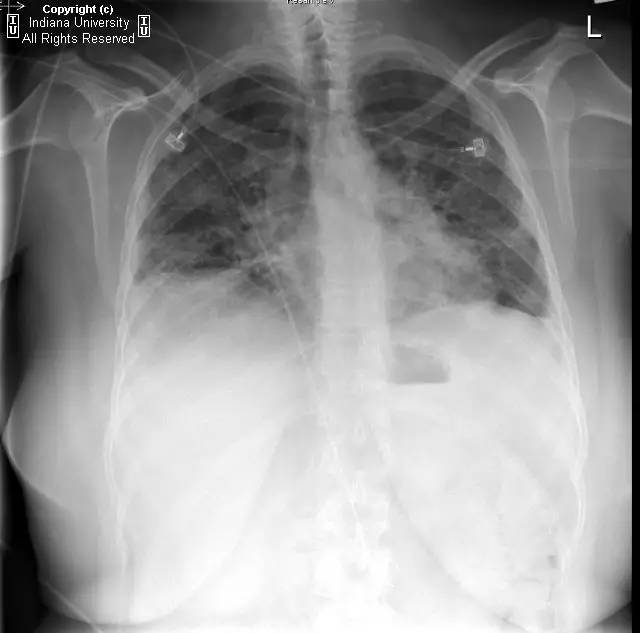

【影像学表现】胸片示双肺纹理增多,间质性透光度减低。无局灶性病变,气胸或胸腔积液。心脏及纵膈轮廓正常。CT示双肺弥漫间质性病变,累及所有肺叶,以下叶为著。肺间质增厚,结构扭曲,牵拉性支气管扩张,外周呈蜂窝状改变。肺动脉增粗,符合肺动脉高压。